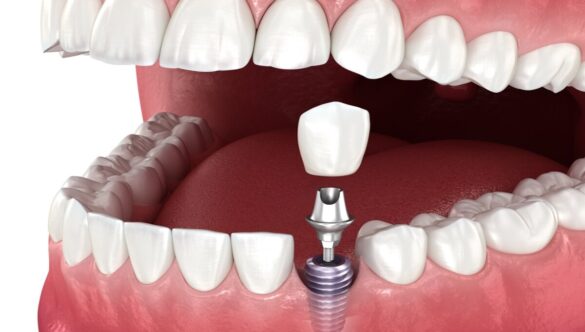

Treatments At Our Dental Clinic in Gandhinagar

Whether you’re searching for a “toothache treatment near me”, “best dental implants near me”, or simply need a trusted dental clinic near you in Gandhinagar, Nova Dental Hospital has the right solution.

DR. HAPPY PATEL is a dental surgeon with 10 years of expertise. She is the owner and director of NOVA Dental Hospital. Her area of expertise is all dental treatments like dental implants, cosmetic dental treatments and smile makeovers, painless root canal treatments, full mouth rehabilitation treatments, fixed and removable dentures, and child dental care.